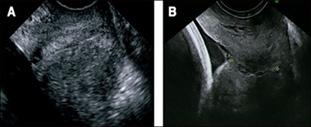

La ecografía del II trimestre (20-24 semanas) permite el diagnóstico morfológico (biometría fetal), importante para detectar malformaciones de los diferentes órganos y sistemas. Los defectos más fácilmente detectados son del sistema genitourinario y de tubo neural. Las cardiopatías hoy en día no son difíciles de diagnosticar. La tasa de detección de cardiopatías puede llegar a ser entre 60 a 80%. El higroma quístico corresponde principalmente a una malformación del 2do trimestre que se asocia con síndrome de Turner (monosomía 45, X0).

La ecografía del III trimestre (30-34 semanas) valora el crecimiento fetal (talla y peso), la localización de la placenta y el volumen del líquido amniótico.

Figura 37. Ecografía de II trimestre Defectos de tubo neural (signo de cabeza de limón) Figura 38. Ecografía de III trimestre Localización de la placenta